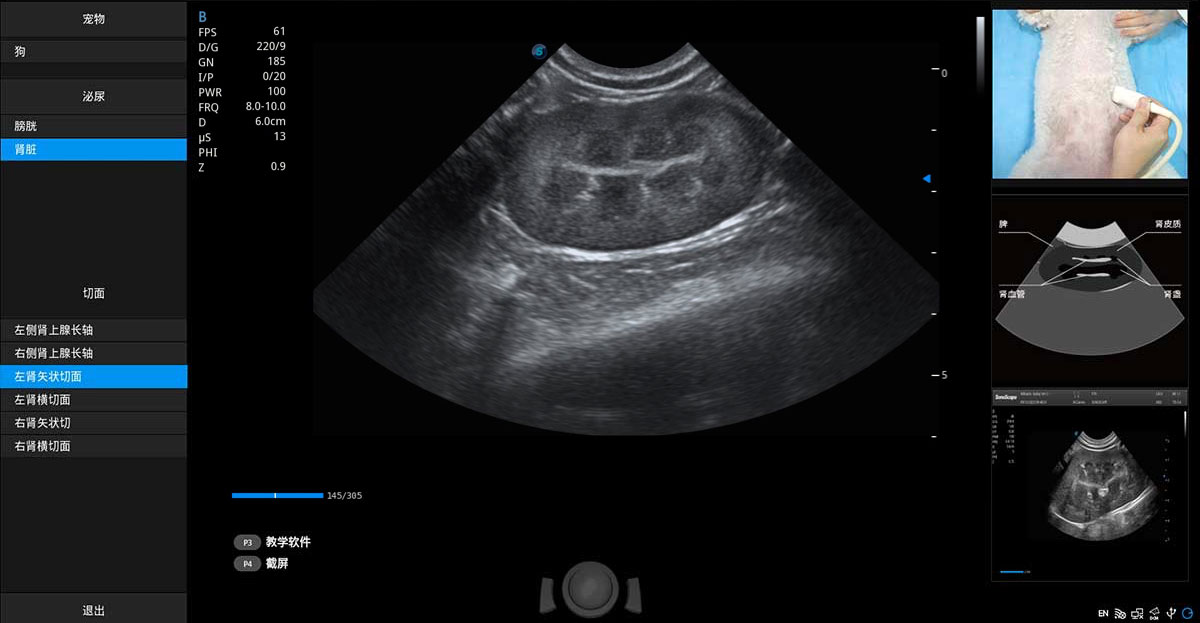

提供解剖示意圖、標準超聲圖像、掃查手法涂和操作者實時檢查圖像,指導(dǎo)操作者進行標準切面的正確掃查。

ProPet 80 專為動物醫(yī)生設(shè)計,對不同的動物體型和生理結(jié)構(gòu)作出了針對性的優(yōu)化。通過動物影像專用軟件,可滿足個性化的應(yīng)用需求,幫助動物醫(yī)生獲得更精確的診斷數(shù)據(jù)。

ProPet 80 全新的動物超聲智能軟件和豐富的探頭群,為動物醫(yī)生提供了高清晰度和精細分辨率的圖像,無論在寵物、馬科、畜牧還是實驗室動物等應(yīng)用中都可以輕松應(yīng)對,為您的日常工作帶來滿意的體驗。